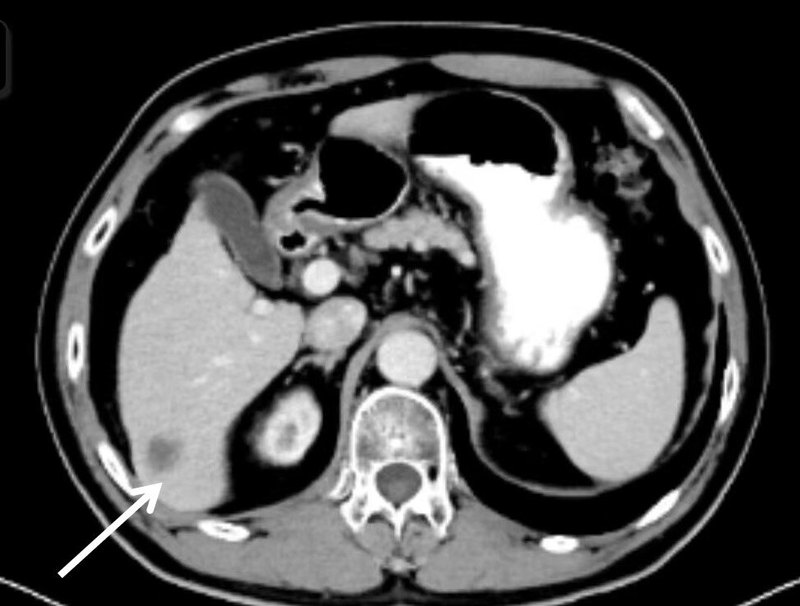

如果發(fā)現(xiàn)肺占位,考慮肺癌可能性大,需要完善哪些檢查?1.?完善血液學(xué)檢查:血常規(guī),肝生化、腎功、糖脂、電解質(zhì),血凝,病毒學(xué),腫瘤標(biāo)志物等檢查。血常規(guī)主要看患者是否白細(xì)胞(如果白細(xì)胞可能存在感染)、血紅蛋白(貧血通常發(fā)生于造血障礙或腫瘤負(fù)荷較大時)、血小板(若血小板低,影響凝血及抗腫瘤治療)。肝生化、腎功、糖脂、電解質(zhì),這個主要是評估患者肝臟及腎臟的功能,大多數(shù)藥物經(jīng)過肝臟和腎臟排泄;很多腫瘤患者合并糖尿病,而血糖異常不利于腫瘤的控制。病毒學(xué):主要看患者是否有病毒復(fù)制,臨床上經(jīng)常發(fā)現(xiàn)患有乙肝而自己不知道的患者,而如果病毒活躍,需要抗腫瘤治療后待病毒復(fù)制倍數(shù)下降至安全范圍,再給予抗腫瘤治療。腫瘤標(biāo)志物,可以對病理分型有指導(dǎo)意義,比如鱗狀細(xì)胞抗原升高通常見于鱗癌,胃泌素前體升高通常見于神經(jīng)內(nèi)分泌癌。2.?病理確診:通常需要CT/B超引導(dǎo)下肺穿刺,氣管鏡取,原發(fā)灶不好取時,會考慮取轉(zhuǎn)移灶。主要目的:一是明確是否為惡性腫瘤,二是如果是惡性腫瘤,需要進一步明確病理分型。病理類型不同,治療原則不同??傮w分為小細(xì)胞肺癌和非小細(xì)胞肺癌。小細(xì)胞肺癌惡性度侵襲性強,惡性度更高;非小細(xì)胞肺癌又分為腺癌、鱗癌等。取病理前若患者口服阿司匹林,需要停用5-7天。3.完善胸上腹部強化CT:肺癌患者肝轉(zhuǎn)移發(fā)生率較高,典型的轉(zhuǎn)移強化CT可診斷,但有時強化CT發(fā)現(xiàn)占位,性質(zhì)不好確定時,需要加做MRI檢查。盡管胸部CT可掃描到一部分肝臟,但不能掃描完全,那么會漏掉部分位置靠下的病變,如下圖所示,因此強烈建議上腹部強化CT做一下。4.頸部B超或CT:部分患者會出現(xiàn)頸部淋巴結(jié)轉(zhuǎn)移,有部分患者會自己摸到頸部腫塊,而有些轉(zhuǎn)移較小時,無癥狀,建議頸部強化CT一起掃描,但若經(jīng)濟條件一般,B超在診斷頸部淋巴結(jié)時有一定優(yōu)勢,也可行頸部淋巴結(jié)B超檢查。5.顱腦核磁共振(MRI):?在診斷腦轉(zhuǎn)移方面,MRI優(yōu)于強化CT,優(yōu)于PETCT。因為MRI排隊時間較長,患者和家屬有時會著急,要求行CT檢查,可先CT粗查,若發(fā)現(xiàn)結(jié)節(jié),再行MRI檢查。如果患者有金屬不能行MRI檢查,或不能靜臥較長時間,則可以強化CT檢查。腺癌和小細(xì)胞肺癌較容易發(fā)生腦轉(zhuǎn)移,還是強烈建議MRI檢查。(如下圖所示)6.骨掃描:顧名思義就是對全部骨骼進行掃描,是核素檢查,檢查完患者短時間內(nèi)帶有輻射性。骨掃描能發(fā)現(xiàn)或排除大多數(shù)的骨轉(zhuǎn)移,但有部分骨轉(zhuǎn)移患者,骨掃描不能發(fā)現(xiàn)異常。(下圖為借鑒網(wǎng)絡(luò)圖片)如果有癥狀或性質(zhì)不易鑒別時,建議做相應(yīng)部位的MRI檢查。7.PET-CT(可選):有助于評估病變范圍,全身功能顯像,該檢查是強烈推薦的。但是由于本項檢查價格較高,不報銷,因此患者和家屬根據(jù)自己的經(jīng)濟條件來,不用過于勉強。但是當(dāng)病變性質(zhì)不易確定,影響分期時,建議還是盡量做一下,因為準(zhǔn)確分期對患者預(yù)后很重要。8.基因檢測(部分患者):主要是針對肺腺癌、鱗癌和肉瘤樣癌。靶向治療改變了肺癌的治療模式,但靶向治療往往是針對特應(yīng)的靶點,需要基因檢測去明確是否存在敏感突變。檢測的基因數(shù)不同,價格和等待時間是有差異的,做檢測之前可與主管醫(yī)師充分溝通?;驒z測一般用CT穿刺和氣管鏡取得的病理組織做(通常不用重新取檢)。9.程序性死亡因子配體1(PD-L1,部分患者):免疫檢查點抑制劑治療自2015年改變肺癌治療模式,極大延長患者生存,通常PD-L1表達(dá)高的療效更優(yōu),低的療效差一些,建議做該項檢查以指導(dǎo)是否免疫治療以及是免疫單藥還是聯(lián)合治療。一般用CT穿刺和氣管鏡取得的病理組織做(通常不用重新取檢)。以上檢查基本是為了評估肺癌的病理分型和分期,而精準(zhǔn)適宜的治療前提準(zhǔn)確分期和分型,不能以癥狀來判斷是否存在轉(zhuǎn)移,因為很多轉(zhuǎn)移病變是無癥狀的,等有癥狀時往往比較嚴(yán)重了。檢查內(nèi)容有時會略有差異,有所增補或刪減,以與主管醫(yī)師溝通為準(zhǔn)。